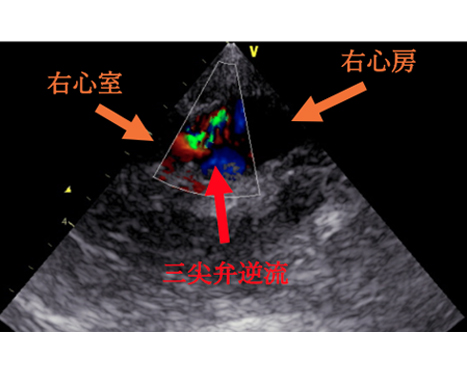

今回の⼼臓超⾳波検査では、 三尖弁からの⾎液の逆流が以前よりも増えていることが確認されました。 また、右⼼室の圧⼒が⾼くなり、左⼼室が押されて細く⾒えるような所⾒や、肺動脈の拡張も認められました。現在、⽇常⽣活で症状はありませんが、⼼臓への負担が以前より増えている状態のため、肺の⾎管を広げて⼼臓の負担を軽減するお薬の内服を始めることになりました。

わんちゃんの⼼臓は、右⼼房/右⼼室・左⼼房/左⼼室という 4 つの部屋からできていま

す。それぞれの間には⾎液が逆流しないように「弁」があります。そのうち、右⼼房と

右⼼室を隔てているのが「三尖弁」です。

これらの原因によって肺動脈の圧⼒が⾼くなると、右⼼室に負担がかかり、その結果、

三尖弁から⾎液が逆流するようになる場合があります。